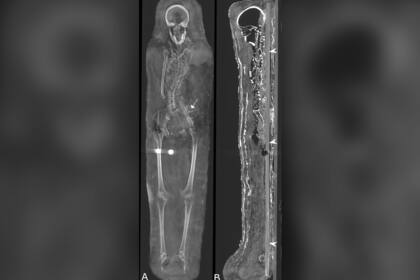

Los escaneos similares a las tomografías computarizadas a los que fueron sometidas las momias revelaron datos sorprendentes. Al menos una de estas tres fue enterrada con sus órganos vitales, incluso el cerebro, y que los cuerpos de las dos mujeres fueron decorados con hermosos collares al momento de la sepultura.

Además de los elementos que acompañaban a las momias, las tomografías computarizadas revelaron distintos problemas médicos, incluida la artritis en la mujer. "El examen de los individuos reveló que eran muy jóvenes al momento de la muerte, sin embargo, no se pudo determinar la causa de la misma", sostuvo Zesch al sitio WordsSideKick.com, declaraciones que reproduce Live Science

El estudio reveló que el hombre murió entre los 25 y los 30 años. Medía 1,64 metros, tenía dos dientes permanentes sin erupcionar y varias caries. Además, algunos de los huesos estaban quebrados y mezclados, probablemente, porque alguien desenvolvió el cuerpo poco después del descubrimiento de la momia.

"Estamos seguros de que no se extrajo el cerebro ni los órganos internos de estas momias. Es muy probable que solo se hayan conservado debido a una especie de deshidratación con el uso de natrón [,mezcla especial para este tipo de procedimientos}, pero no hay una gran cantidad de líquidos de embalsamamiento", precisa Zesch.

Por su parte, la mujer debe haber muerto entre los 30 y los 40 años y medía 1,51 metros. Tenía artritis avanzada en la rodilla izquierda. La adolescente, que llevaba un tocado, de acuerdo con la tomografía computarizada, murió entre los 17 y los 19 años y su estatura era de 1,56 metros. Tenía un tumor benigno en la columna conocido como hemangioma vertebral, que es más común en personas adultas.